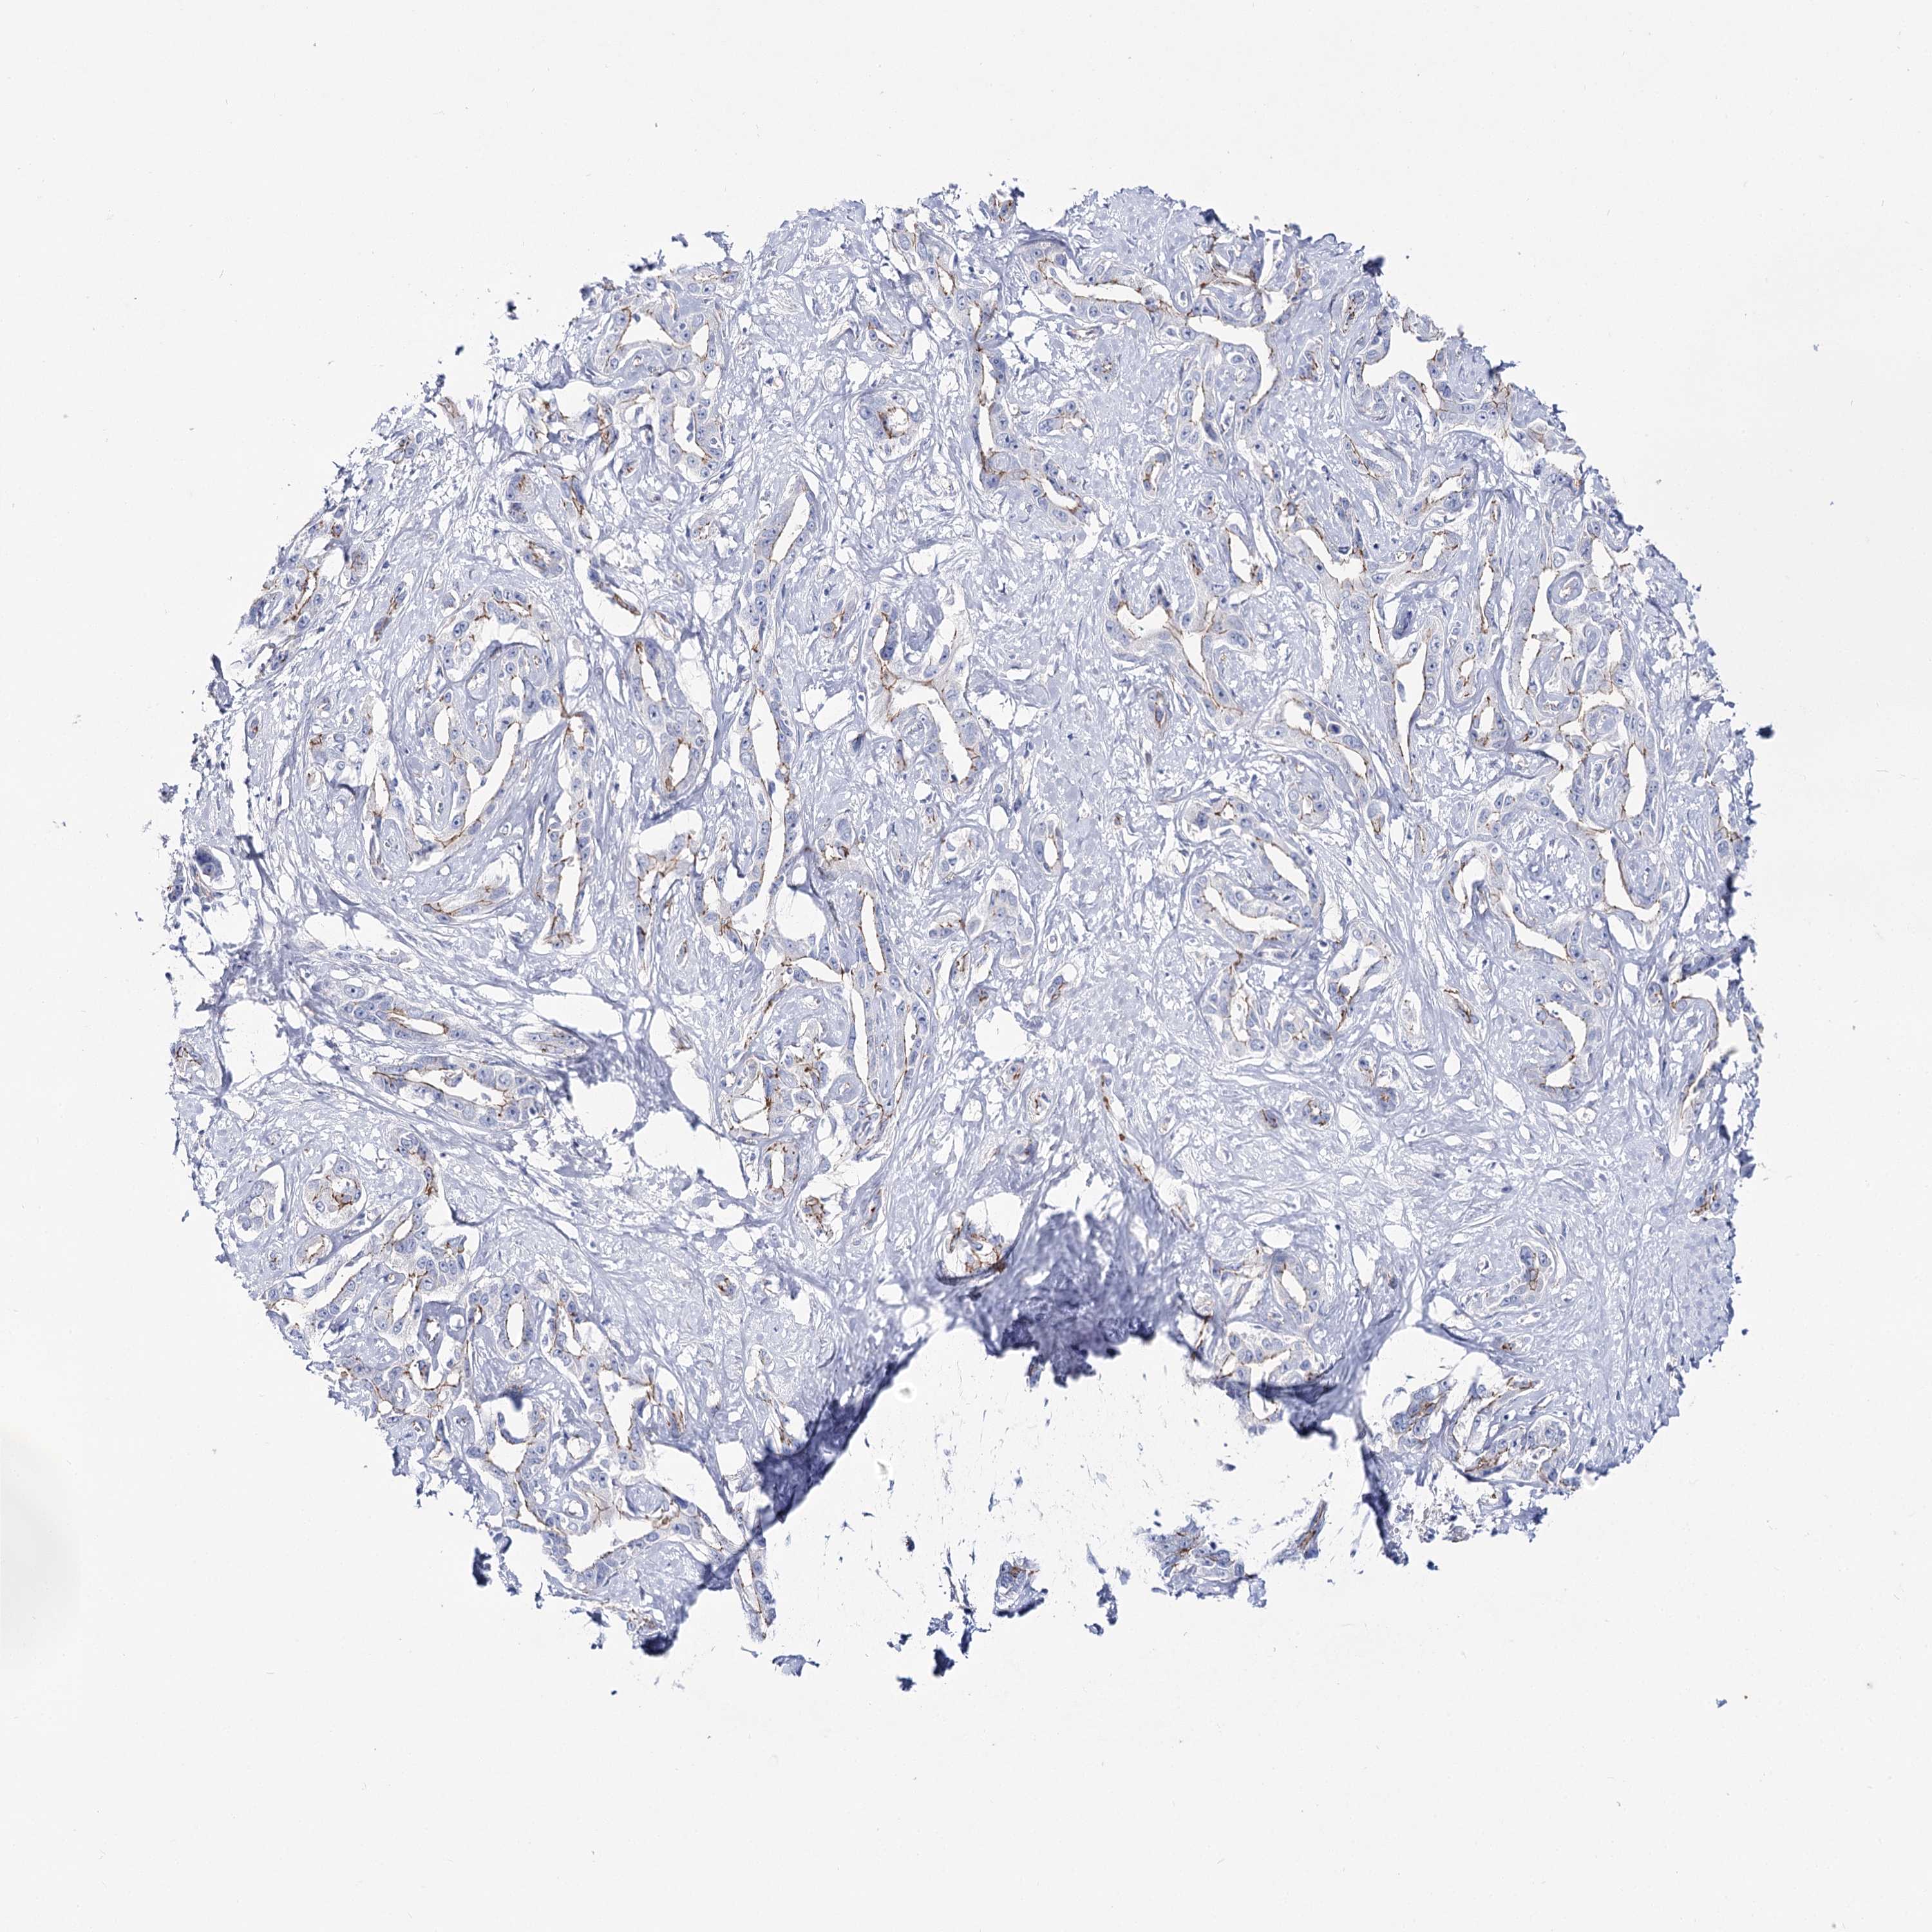

LIVER CANCER - Protein expressioni

A mouse-over function shows sample information and annotation data. Click on an image to view it in a full screen mode. Samples can be filtered based on level of antibody staining by selecting one or several of the following categories: high, medium, low and not detected. The assay and annotation is described here.

Note that samples used for immunohistochemistry by the Human Protein Atlas do not correspond to samples in the TCGA dataset.

Antibody stainingi

Antibody staining in the annotated cell types in the current human tissue is reported as not detected, low, medium, or high, based on conventional immunohistochemistry profiling in selected tissues. This score is based on the combination of the staining intensity and fraction of stained cells.

Each image is clickable and will lead to virtual microscopy that enables deeper exploration of all samples and also displays staining intensity scores, fraction scores and subcellular localization as well as patient and tissue information for each sample.

Antibody HPA037953

Antibody HPA037954

Staining

High

Medium

Low

Not detected

Intensity

Strong

Moderate

Weak

Negative

Quantity

>75%

75%-25%

<25%

None

Location

Nuclear

Cytoplasmic/membranous

Cytoplasmic/membranous,nuclear

Cholangiocarcinoma

Carcinoma, Hepatocellular, NOS